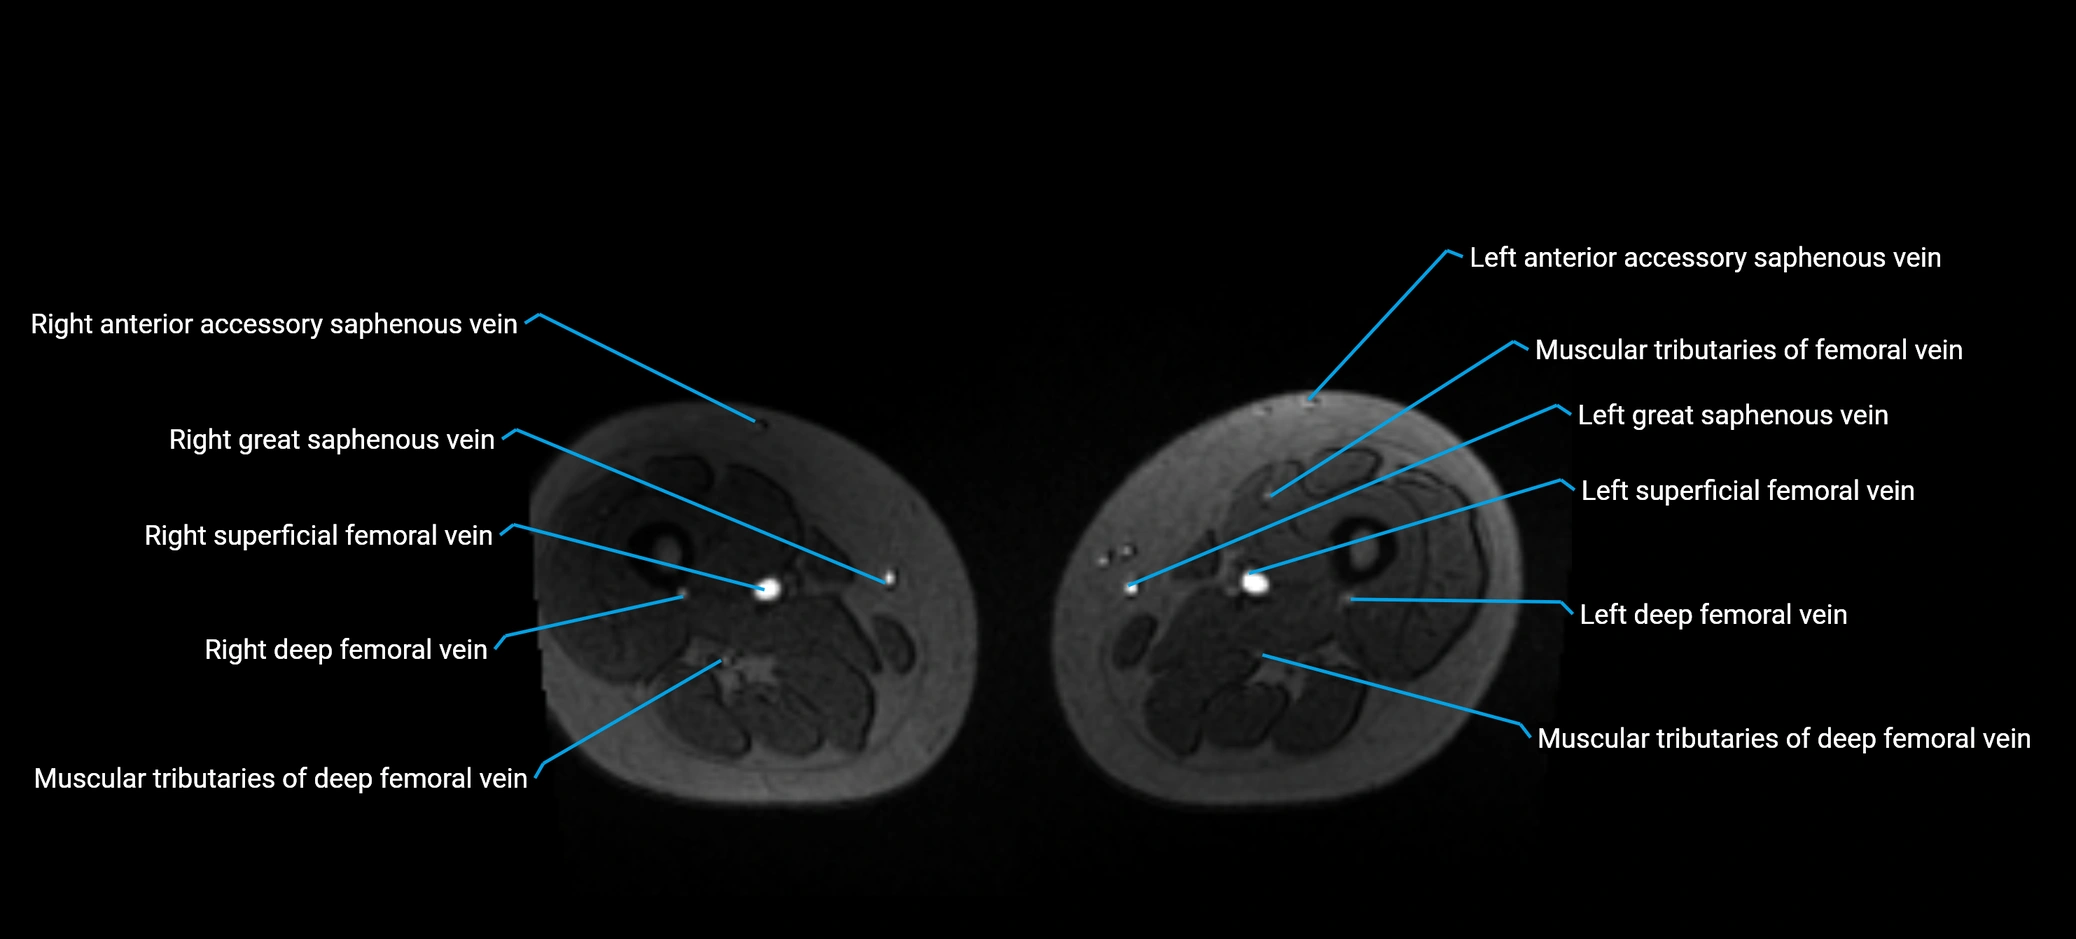

MRI image

image